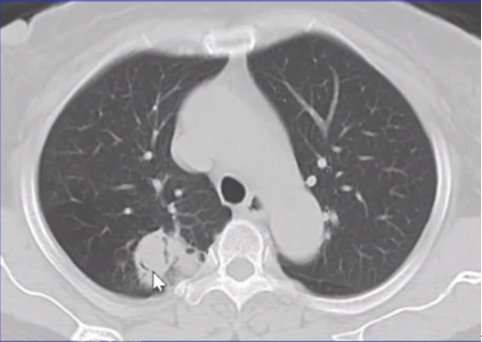

曲霉的破坏程度与曲霉菌丝生长相对成比例,其破坏范围形成的坏死、空洞及分隔均少于毛霉,而毛霉的破坏力更强。下图是一个结节,周边有晕征,说明病变是血管侵袭性,其中有很多小气泡,没有液平面,说明有菌丝的存在,菌丝固定了坏死物。但纵隔窗看到分隔特别粗大,小气泡特别大,说明坏死占的比例更多,坏死程度更严重,而菌丝的生长与坏死程度不成比例,所以是“坏死多菌丝少”,这是毛霉的特征。而曲霉感染则是“坏死多菌丝多”,坏死物相对固定,小气泡并未形成大的空洞。这也是曲霉和毛霉重要的鉴别点(图22)

图片

图22  毛霉和曲霉感染坏死、空洞的区别

注:A、B为毛霉所致病变,空洞内分隔粗大不均,空洞更大;C为曲霉所致坏死物固定,小气泡多。